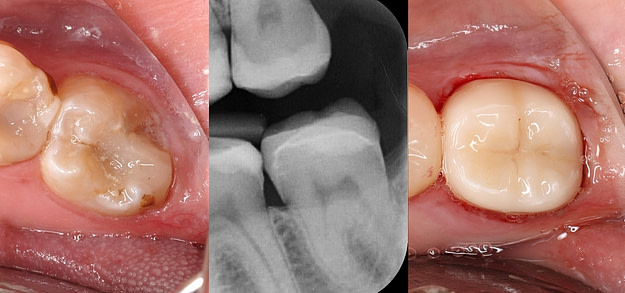

Precision and Accuracy

Digital technologies allow for extremely precise measurements and fabrication of dental restorations. This precision leads to a better fit, which can improve the longevity of the restoration and the overall health of the surrounding teeth and gums.

Speed and Efficiency

Digital restorations can often be designed, fabricated, and placed in a single visit, which is a significant improvement over traditional methods that may require multiple appointments.

Patient Comfort

Digital impressions are generally more comfortable for patients than traditional methods, which often involve physical molds that can be unpleasant and trigger gag reflexes.